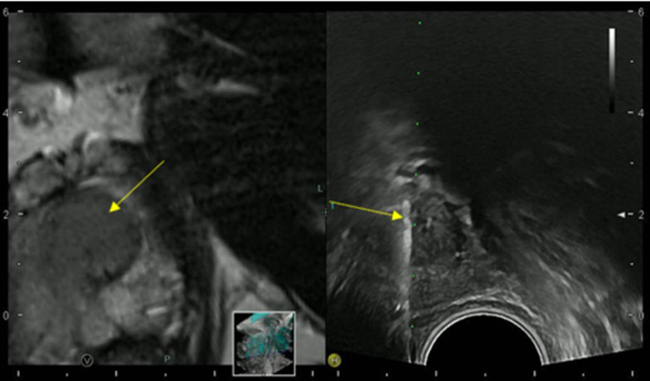

Imaging and Targeted Biopsy of the Genitourinary (GU) Tract

Friedrich Aigner

- Fusion imaging of the GU-tract

- Fusion targeted biopsy of the prostate

The simultaneous application of structural and functional imaging techniques is described as multiparametric (MP) (Fig. 9). Studies have shown that the MP approach results in greater diagnostic accuracy (Fig. 10).

The use of fusion imaging in uroradiology improves ultrasound lesion-detection rates, shows more reliable size controls at different time points, is an alternative to in-bore biopsies (Fig. 11) and can be used for focal therapy.